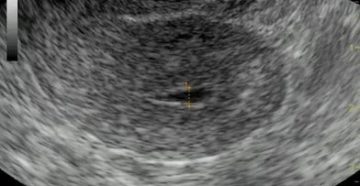

Причины и лечение тонкого слоя эндометрия Что это такое тонкий эндометрий и почему он так…